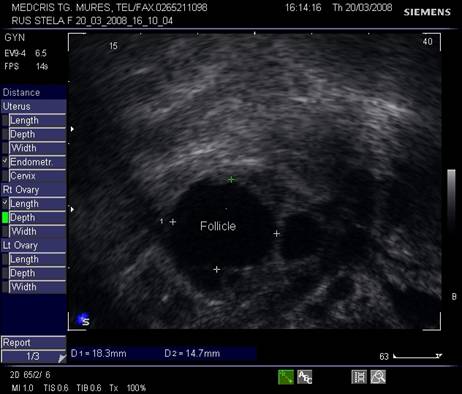

Dupa ziua a 5-7, un folicul ovarian devine dominant , fata de ceilalti ce devin atretici. In ziua 10 -a - 11-a foliculul depaseste 12 mm diametru. Cresterea foliculara de 2 - 3 mm/zi ne duce la un folicul preovulator de cca 21 mm diametru (24 - 26 mm). Doi foliculi dominanti au fost identificati in 10% din ciclurile spontane [8].

Deoarece foliculii sunt ovoidali, diametrul mediu conteaza pentru foliculometria, dupa masurarea a 3 diametre si impartirea la 3.[6]

Semnele ecografice ale ovulatiei iminente [6,9]:

Ovarul:

diametrul folicular peste 20 mm,

detectarea cumulus oophorus in folicul

semnal Doppler la periferia foliculului

Fig. nr.371. Folicul selectat ziua a XI a de ciclu menstrual, la ecografia transvaginala

Fig. nr.372. Folicul preovulator , in care se remarca

cumulus oophorus ( sageata, eco transv.)